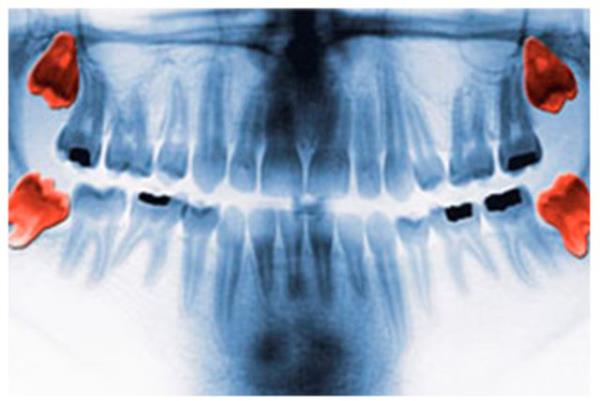

14. <br><b>20 Yaş Dişleri</b></br>  İlk insanlar birçok bitki türüyle besleniyordu ve gün boyunca ihtiyaç duydukları tüm gıdaları almak için yeterli miktarda bitkiyi, yeterince hızlı şekilde yemeye ihtiyaç duyuyorlardı.

20 Yaş Dişleri

İlk insanlar birçok bitki türüyle besleniyordu ve gün boyunca ihtiyaç duydukları tüm gıdaları almak için yeterli miktarda bitkiyi, yeterince hızlı şekilde yemeye ihtiyaç duyuyorlardı.

15. Bu sebeple, daha geniş bir ağzı daha üretken kılmak için ilave bir takım azı dişimiz mevcuttu. Selülozun vücut tarafından yeterli şekilde sindirilmesi kabiliyetinden yoksun olunduğu için bu özellikle gerekliydi.

Bu sebeple, daha geniş bir ağzı daha üretken kılmak için ilave bir takım azı dişimiz mevcuttu. Selülozun vücut tarafından yeterli şekilde sindirilmesi kabiliyetinden yoksun olunduğu için bu özellikle gerekliydi.

16. Evrimle gıdalarımız değişti, çenemiz uygun bir şekilde küçüldü ve üçüncü azı dişlerimiz gereksiz hale geldi. Günümüzde bazı insan topluluklarında 20 yaş dişlerinin üretimi tamamen durmuşken, bazı topluluklarda %100 oranda bu dişler çıkmaktadır.

Evrimle gıdalarımız değişti, çenemiz uygun bir şekilde küçüldü ve üçüncü azı dişlerimiz gereksiz hale geldi. Günümüzde bazı insan topluluklarında 20 yaş dişlerinin üretimi tamamen durmuşken, bazı topluluklarda %100 oranda bu dişler çıkmaktadır.